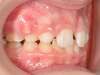

Cas N°6 : Description

Correction majeure des deux arcades dentaires liée à une mandibule rétrusive

Avant

Après